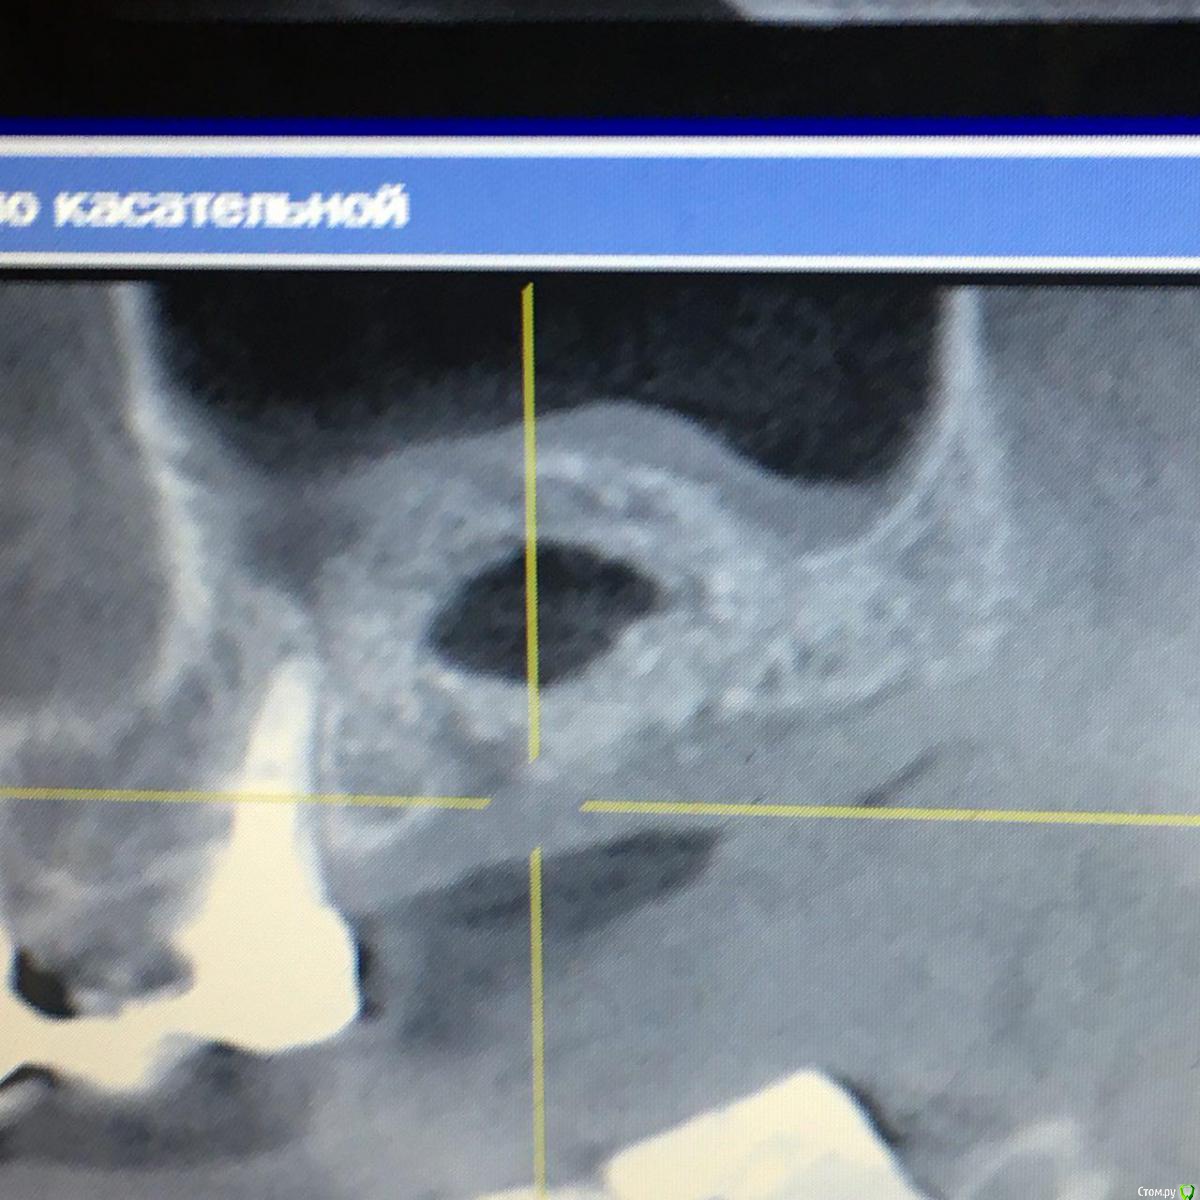

Andre_ Опубликовано 6 сентября, 2018 Автор Поделиться Опубликовано 6 сентября, 2018 Продолжение истории. Во время моего отпуска пациентка с жалобами на боли в зоне интереса попала в ЧЛХ с диагнозом остеомиелит в/челюсти. Где, со слов пациентки, был убран инкапсулировавшийся инфицированный графт, доступом изо рта ( видимо, с остатками пострадавшего альвеоляра, и вероятно перфорнувшись в пазуху). КТ на момент поступления прикладываю. В настоящий момент п/о рана во рту заживает вторично. Пока что пациентка получила частично средства за манипуляции и обещала явиться на КТ контроль. Думаю направить позже ЛОРам, если что. И придумывать НКР + винты. 2 Ссылка на комментарий